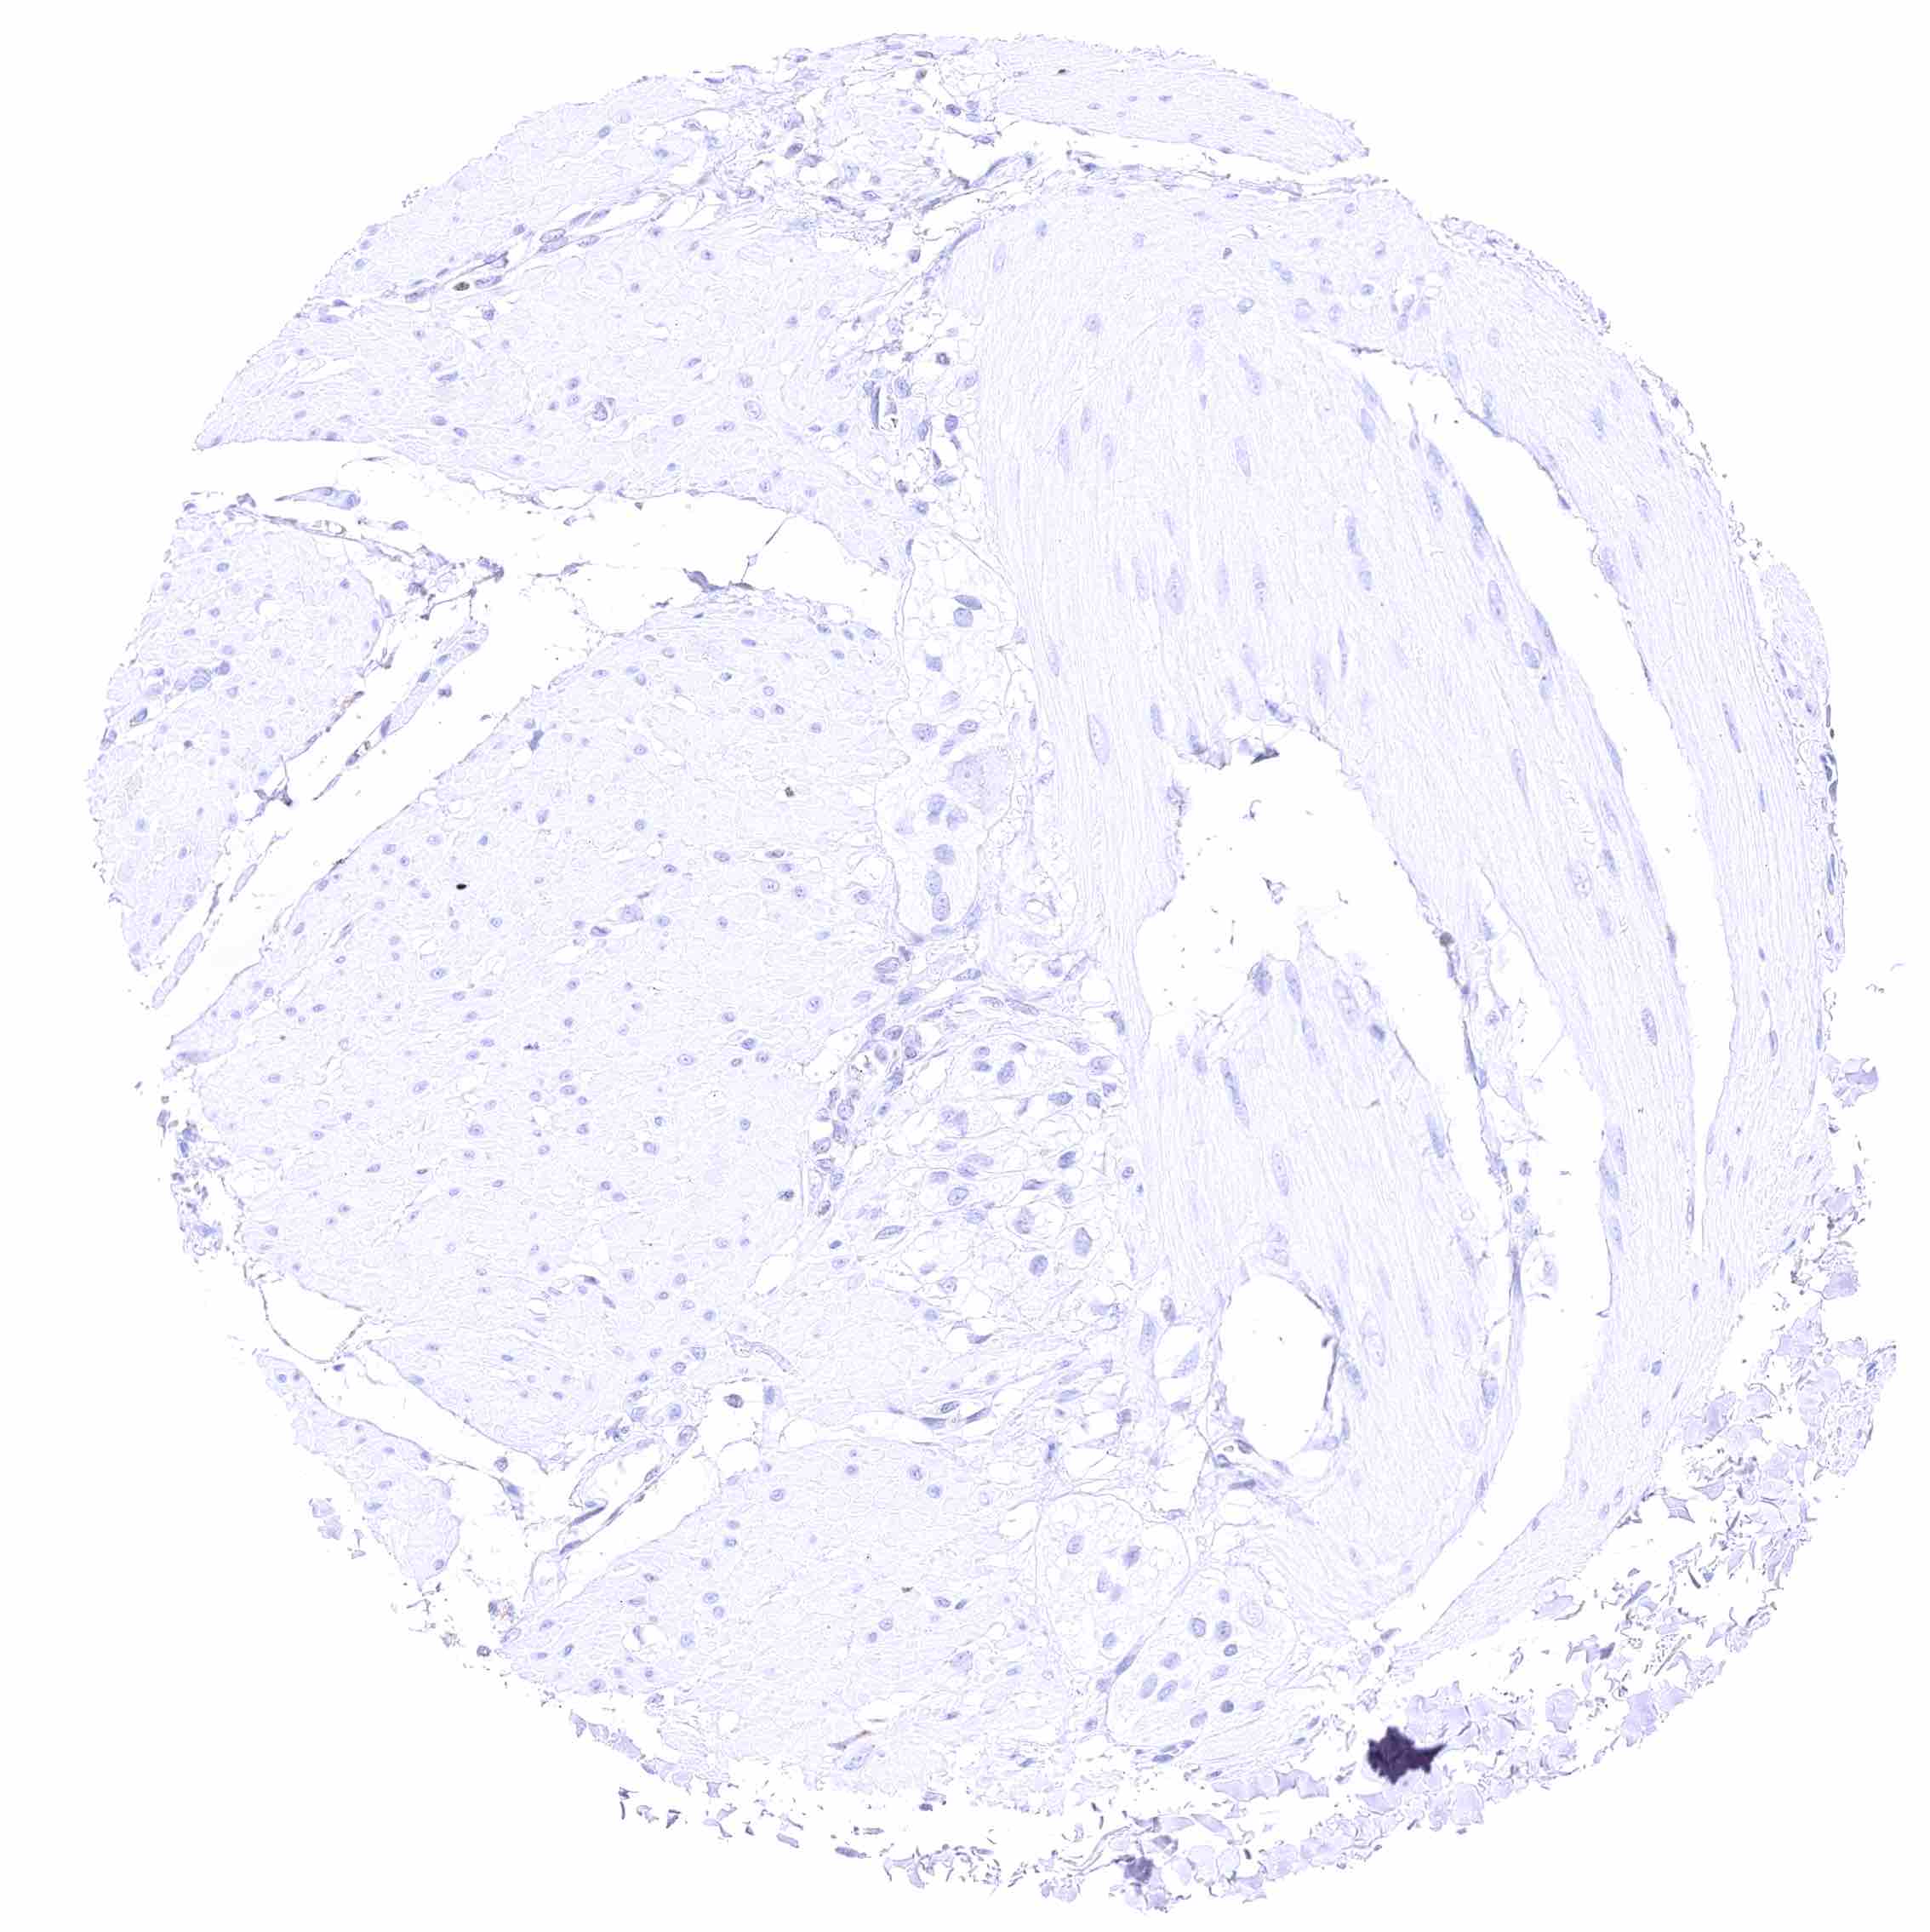

Cerebellum (molecular layer, Purkinje cell layer, granule cell layer)

Cerebellum (white matter)

Cerebrum (grey matter)

Cerebrum (white matter)